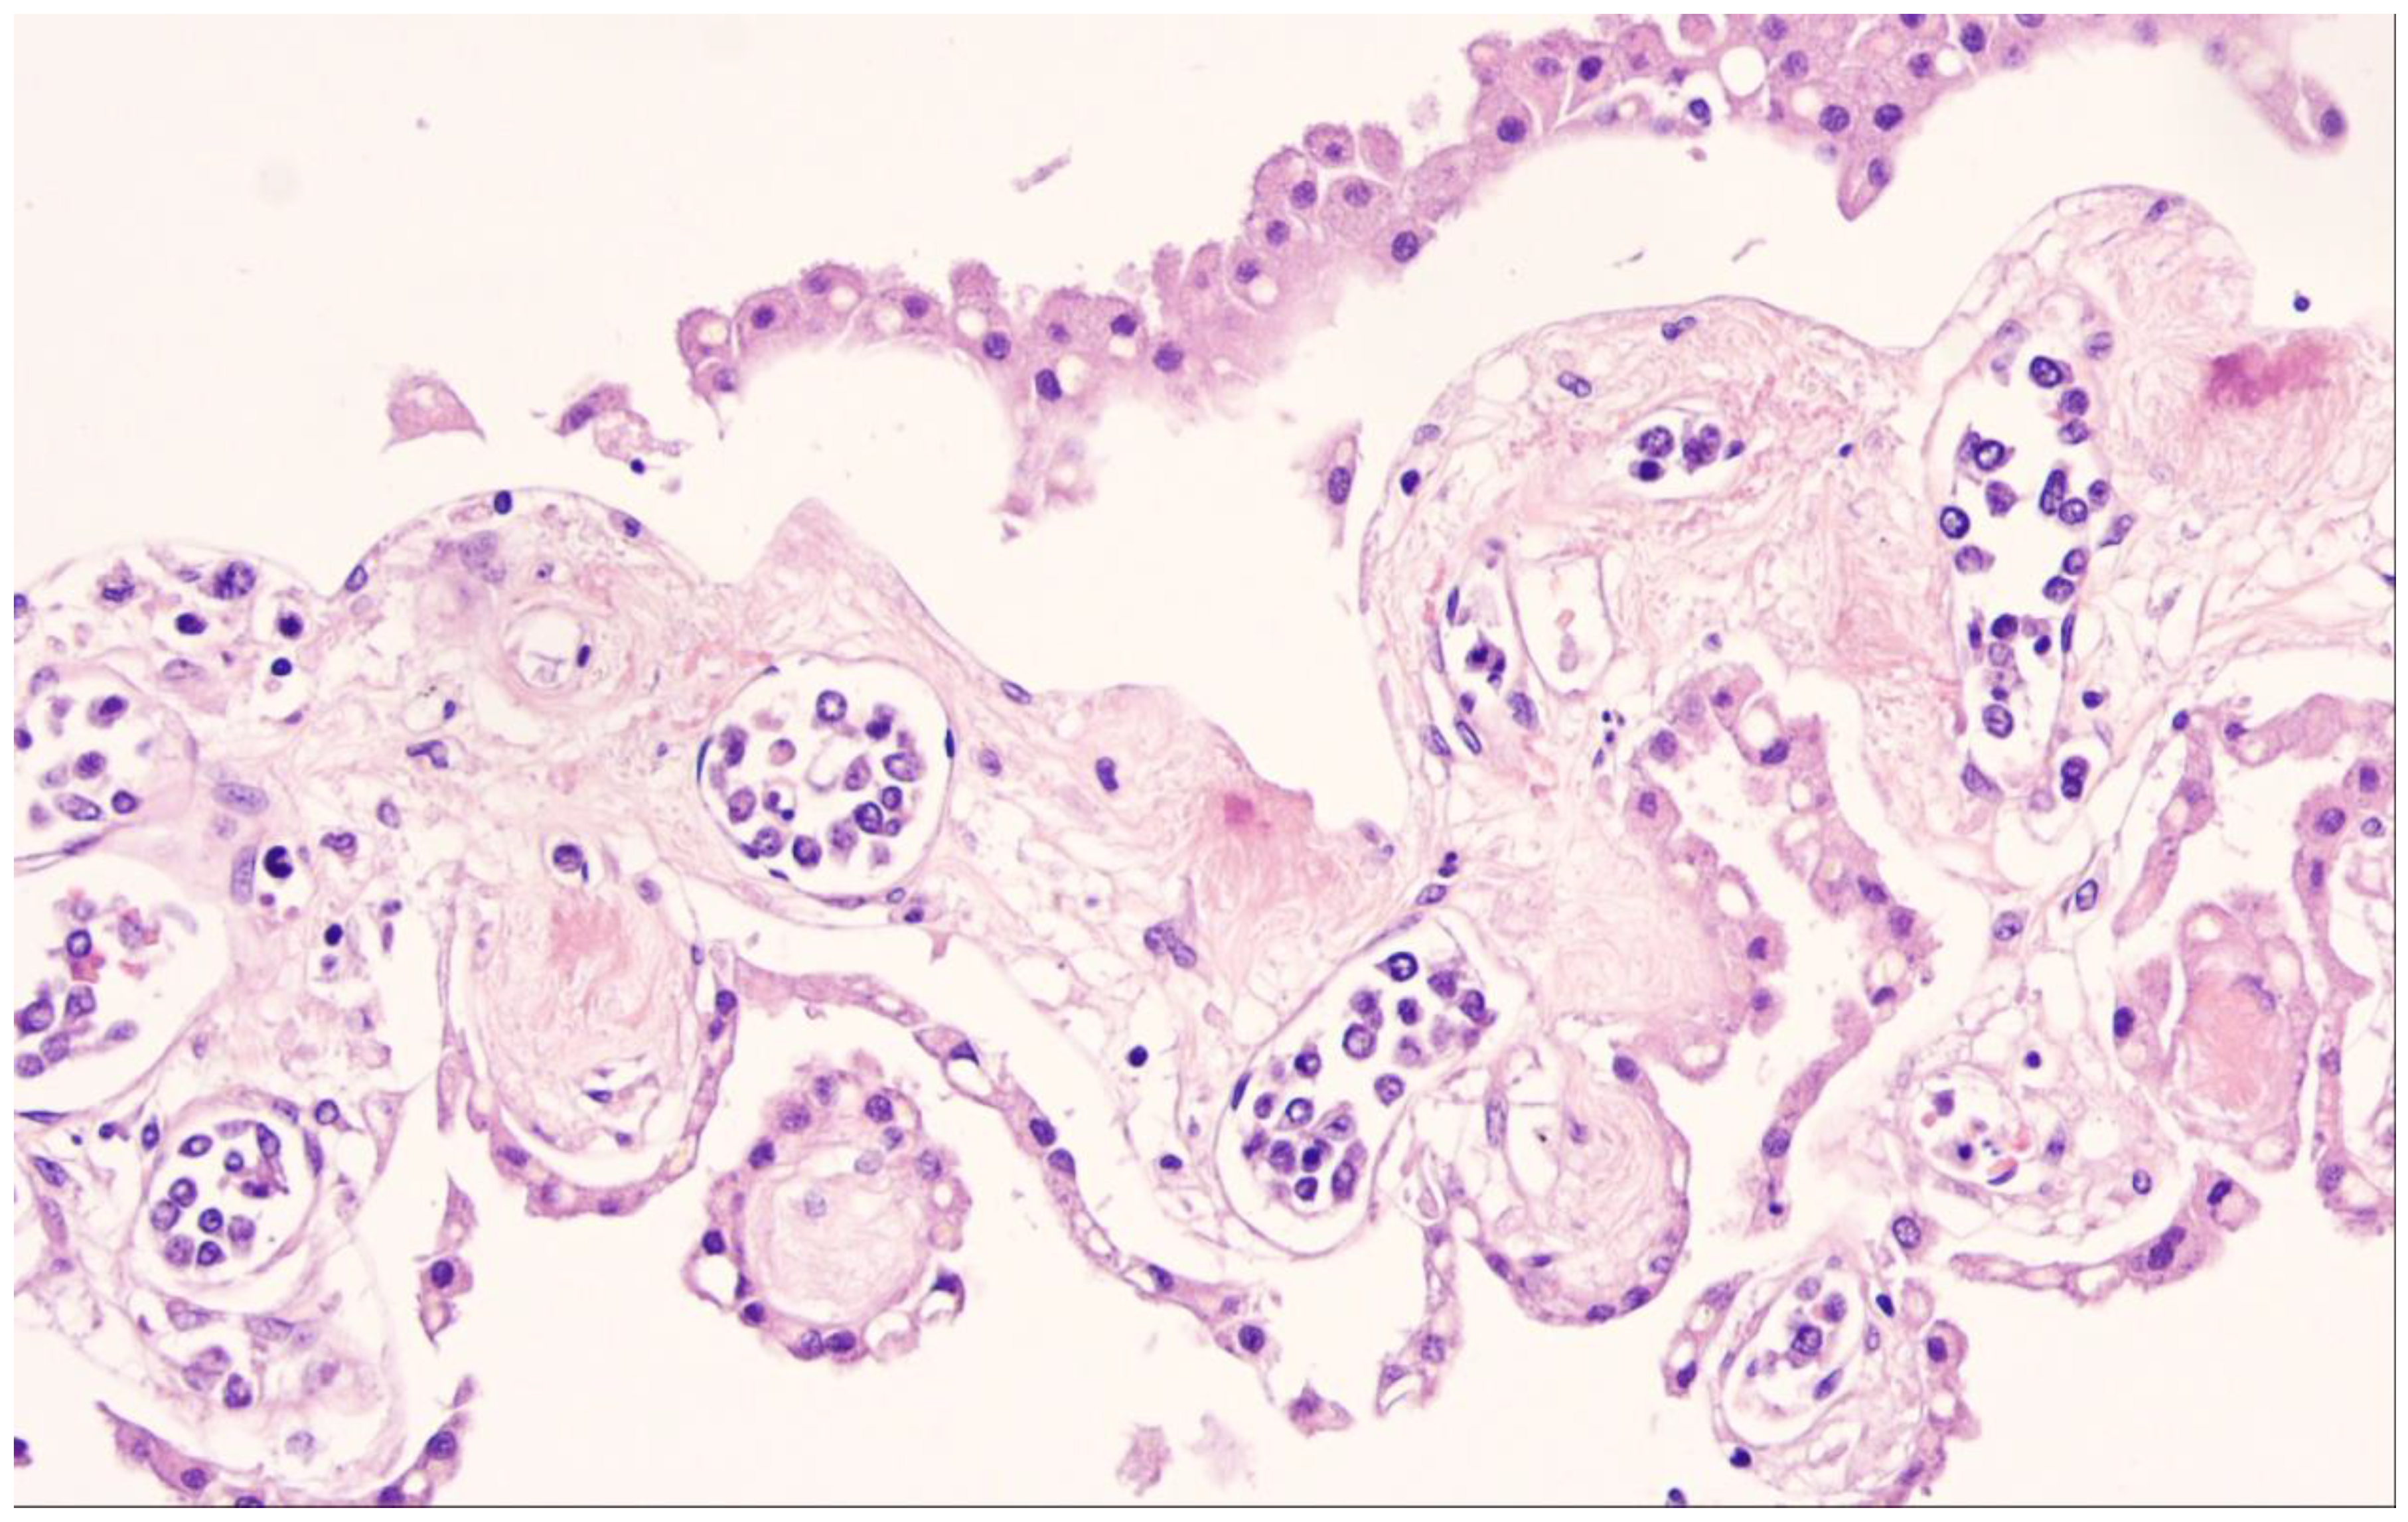

9. Lymphomatoid Granulomatosis

| Lymphomatoid granulomatosis |